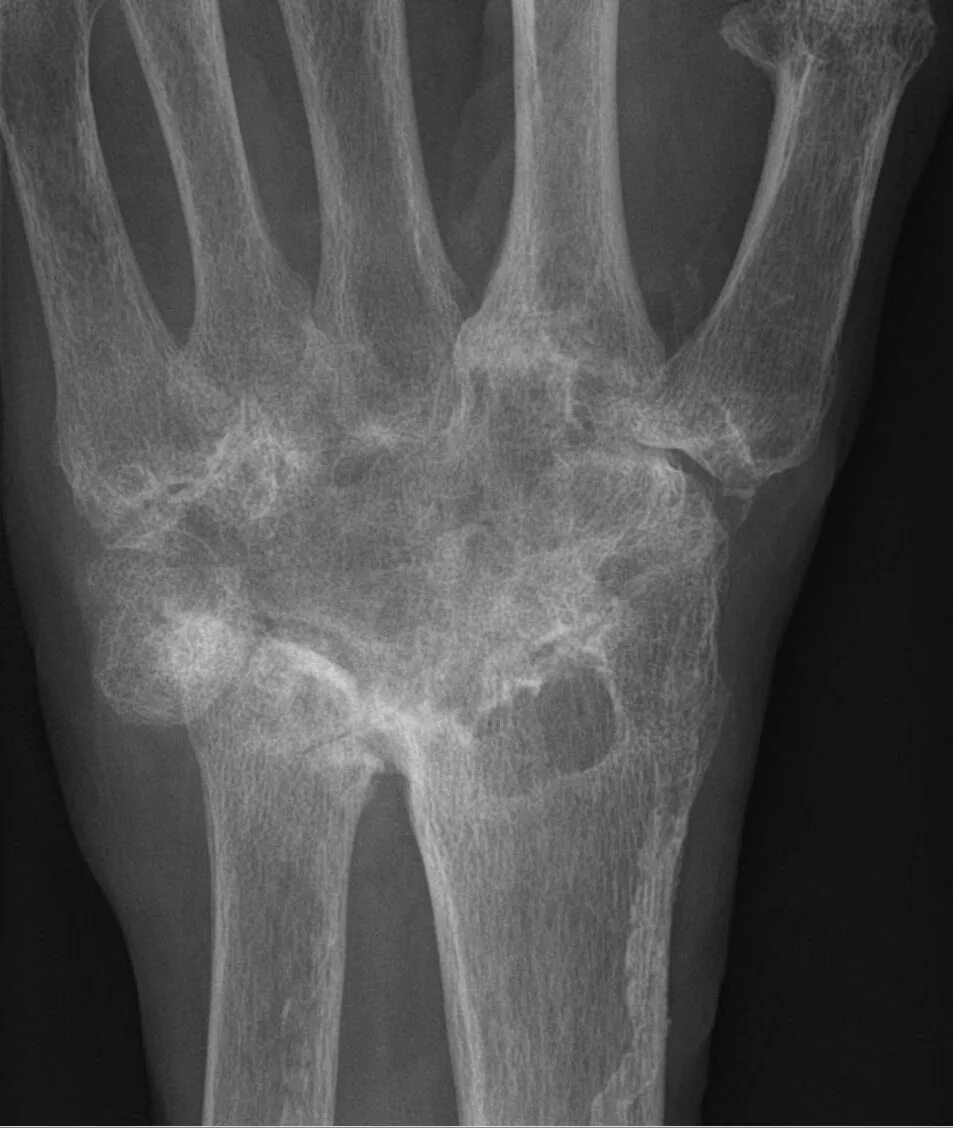

Артроз лучезапястного сустава 2 степени